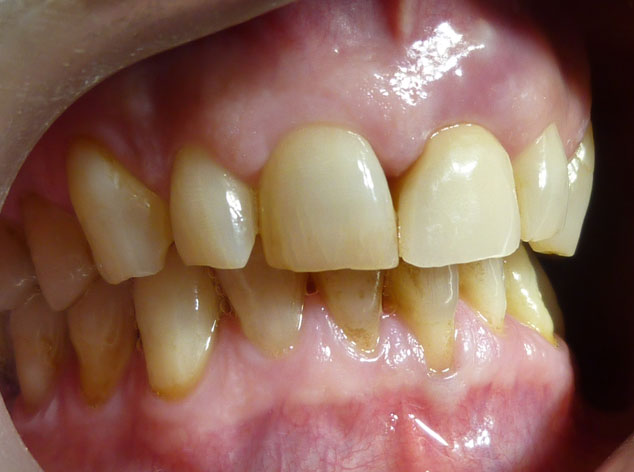

En estos casos han sido tratados con la filosofía de all-at-once, en la

misma sesión: